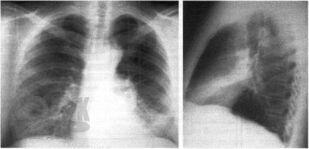

Бронхолегочные синдромы в пропедевтике внутренних болезней

Учебное пособие подготовлено в соответствии с ООП и учебным планом по дисциплине «Пропедевтика внутренних болезней» для обучающихся по специальности 31.05.01 «Лечебное дело». В учебном пособии изложены современные представления об основных синдромах при заболеваниях органов дыхательной системы, необходимых для обучающихся при изучении дисциплины «Пропедевтика внутренних болезней». Учебное пособие оснащено тестовыми заданиями и ситуационными задачами различной степени сложности для самоконтроля знаний с эталонами ответов. Учебное пособие предназначено для самостоятельной внеаудиторной работы обучающихся по специальности «Лечебное дело».